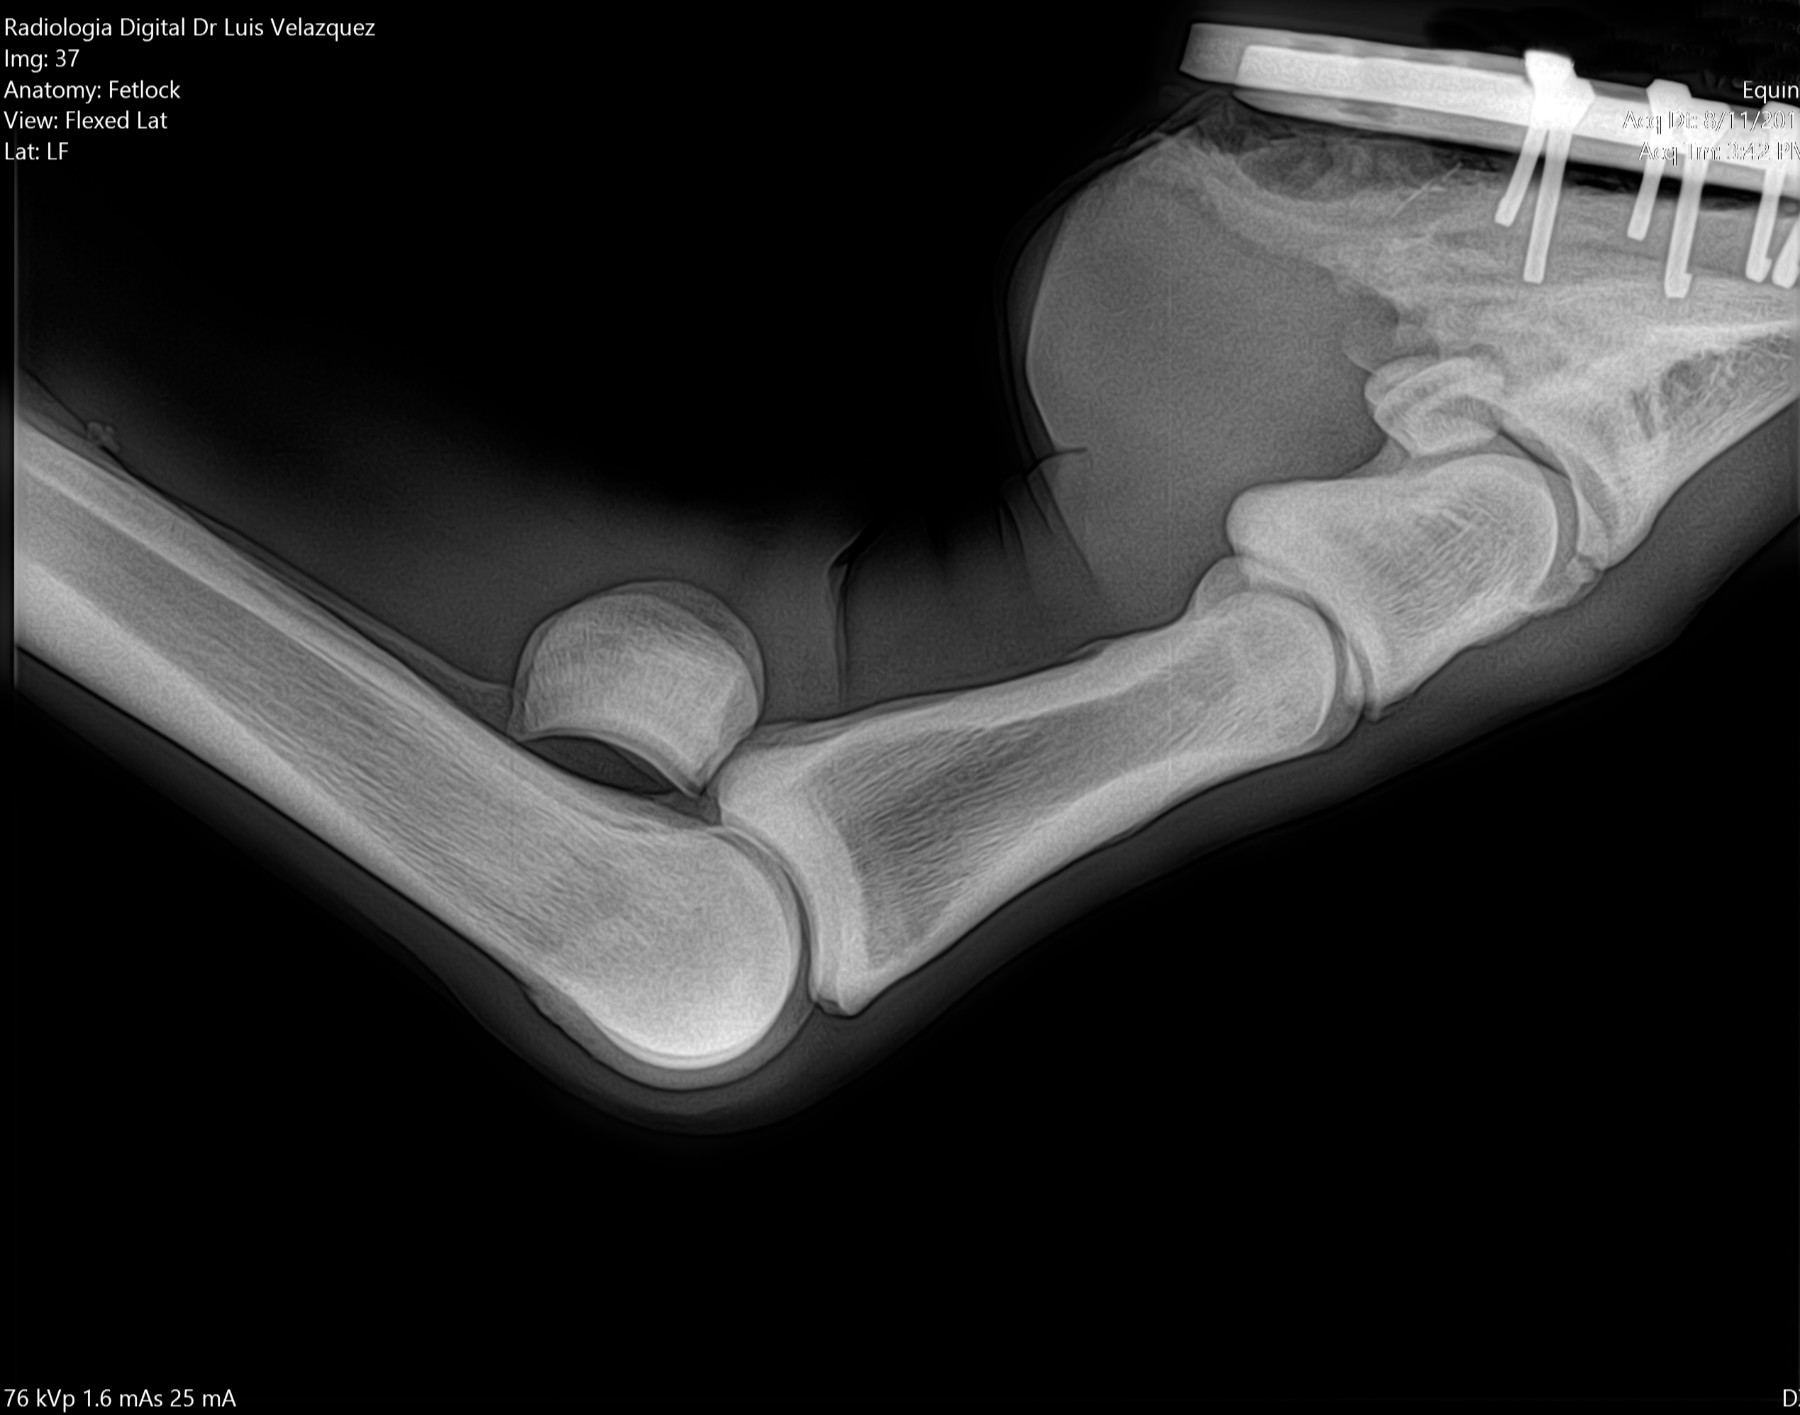

Cambios Térmicos en las Extremidades de Caballos,

Asociados a Golpes y su Evaluación por Termografía.

Los caballos de salto, en competencia, pueden derribar obstáculos y lastimarse. Si se golpean, no siempre claudican. Considerando al calor como un signo de inflamación, se evaluaron los cambios térmicos de 6 áreas de las extremidades torácicas y pelvianas de 23 caballos de salto en nivel de competencia de 1.05 a 1.60 m de altura, por medio de termografía durante 4 días de competencia (N=2208 áreas).